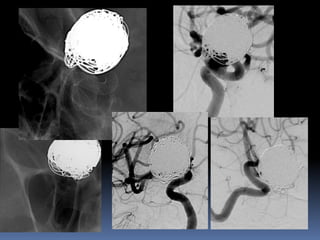

Circumferential involvement-End hole

Broad neck , dyplastic aneurysms

A

B

C

large-/giant aneurysms

Broad neck ,dyplastic aneurysms